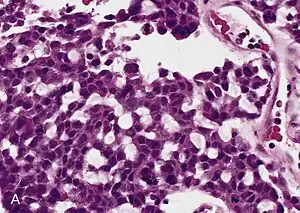

O Câncer de adrenal (carcinoma adrenocortical) é um tumor originado na córtex da glândula adrenal.[1] por ser infrequente (raro), tem uma incidência anual de 0,5/2 casos de 1 000 000,[2] existe um pico de casos em crianças até os 5 anos e adultos na média de 40-50 anos.[3] Geralmente esses tumores começam um excesso produção de hormônios,[2] excesso de produção de catecolaminas e produzir quantidades maiores de cortisol na circulação, o que pode causar distúrbios metabólicos.[4]